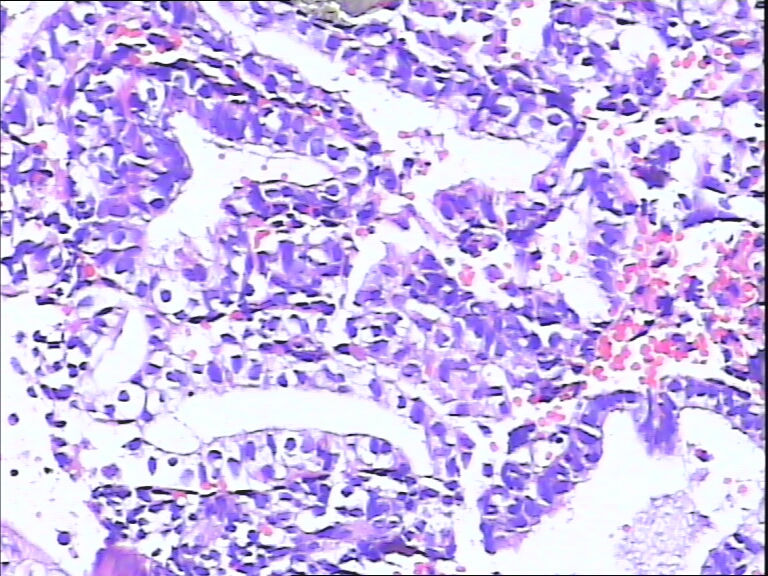

41岁,停经5年再出血。

• 宫内膜图1

图1

流血期子宫内膜,腺体反应不同步。

片子不是很清楚,像是月经期子宫内膜

是不是采图有问题,片子上细胞变形严重,从轮廓看问题不大,至少不是恶性,再传点图

流血期子宫内膜,腺体反应不同步

腺体增生,部分腺上皮有分泌。